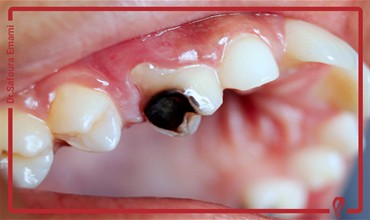

دکتر صفورا امامی متخصص درمان ریشه و عصب کشی

من صفورا امامی، متولد سال ١٣٥٩، متخصص درمان ریشه دندان و دارای رتبه دوم بورد تخصصی اندودانتيكس (درمان ریشه) در بین کلیه دانشكده هاي دندانپزشكی كشور در سال 1396 و در همان سال با عضویت در هـيأت علمی دانشگاه آزاد تهران مشغول به فعاليت شده و هم‎زمان مطب تخصصی خود را افتتاح كردم.